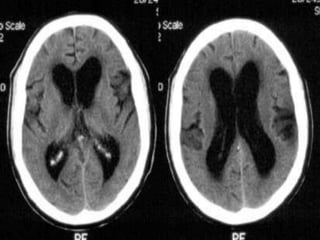

Disoders of CSF spaces

• Hydrocephalus communicating and non

communicating including IIH,NPH.

• Loss of csf spaces usually secondary to

degenerative and other secondary processes.

Disoders of CSFspaces • Hydrocephalus communicating and non communicating including IIH,NPH. • Loss of csf spaces usually secondary to degenerative and other secondary processes.